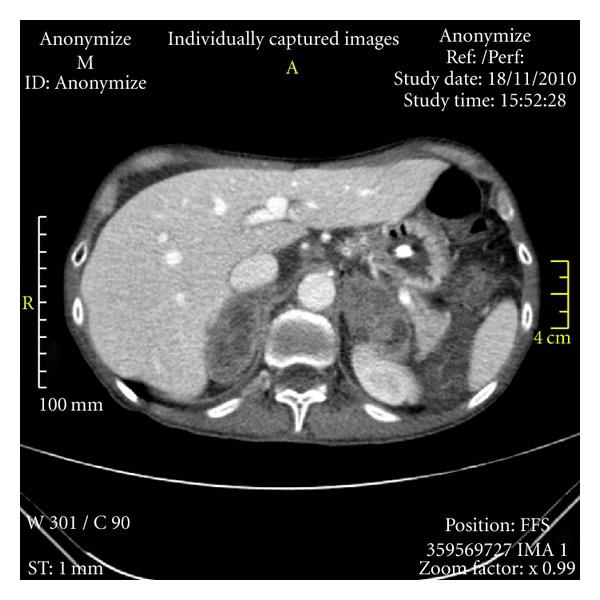

We report a case of a patient with adrenal failure due to bilateral adrenal metastasis of lung cancer. This is a rare presentation of lung cancer. We review the differential diagnosis of weight loss and how to make diagnosis of adrenal insufficiency.

我们报告一例因肺癌双侧肾上腺转移导致肾上腺功能衰竭的患者。这是肺癌的一种罕见表现。我们回顾了体重减轻的鉴别诊断以及如何诊断肾上腺功能不全。